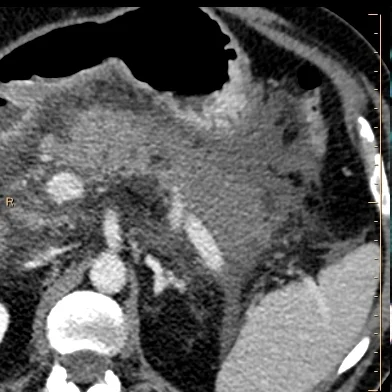

Conventional CT in portal venous phase shows pancreatitis with hypoenhancing body and tail.

CT from 4 weeks later shows large necrotic collection.

Conventional CT shows pancreatitis